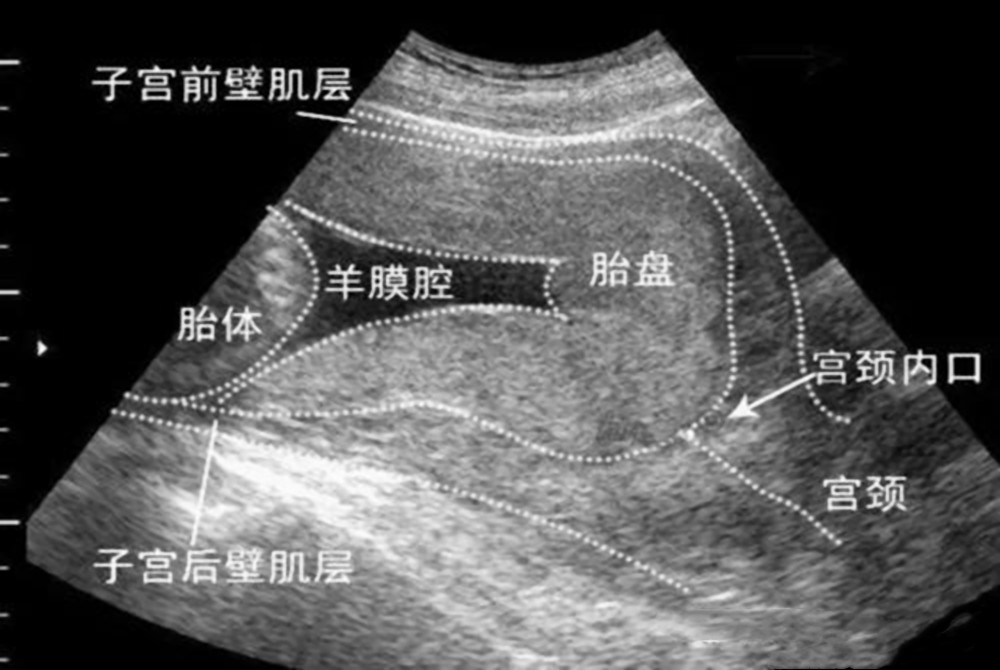

胎盘前壁,是指胎盘的位置,更靠近宝妈的肚皮方向,而不是背部,是正常胎位的一种,相对来说比较安全的。

胎盘前置,是指胎盘的位置,在子宫的最底部,也就是靠近宫颈口的位置,在孕前期的三个月里,胚胎较为柔弱,宝妈就很容易因胎盘前置,出现见红和流产的问题。